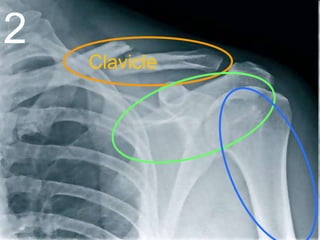

Clavicle

2

Scapula

Humerus